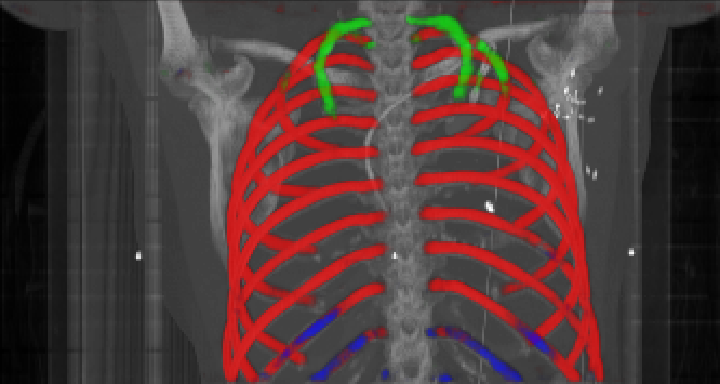

As can be seen from Table 2, we obtain overall good performance for the overall rib detection captured for example with an mean Dice of 0.84. Let us remark that for thin objects, such as the dilated rib centerlines, the Dice score constitutes a rather sensitive measure. The results indicate that detecting the first and twelfth rib pairs is more difficult for our network. While extraction of the first rib is more challenging due to, e.g., higher noise in the upper thorax or other bony structures in close vicinity (clavicle, shoulder blades, vertebrae), the twelfth rib can be extremely short and is easily confused by the neighboring ribs. For further illustration, Figure 4 shows the results on selected representative cases. Generally, the ribs are well detected without major false responses in other structures - despite all the different challenges present in the data. The color coding highlighting of the multi-label detection reveals that first and twelfth are mostly correctly detected. In few cases the network wrongly generated strong responses of the classes first rib or last rib for voxels belonging to the second or eleventh rib pair.

Refer to caption

Figure 4: Maximum intensity projections (MIP) of selected CT volumes overlaid with the multi-label output of the neural network (green: first rib; red: intermediate rib; blue: twelfth rib). The selected case above display common difficulties which are inherent in the data set, such as pads (a) or cables (b), internal devices such as pacemakers (c), stents (d), spinal (e) and femural/humeral implants (f), injected contrast agents (g), patient shape variations such as scoliosis (h), limited field of views (FOVs), i.e. partly missing first (i) or twelfth rib (j).